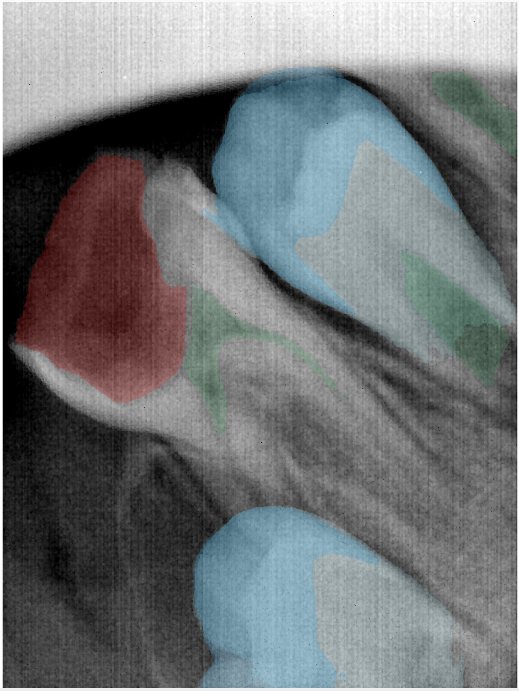

第二版算法问题测试

| 第一版 | 第二版 | 是否解决 | |

|---|---|---|---|

![]() | ![]() ![]() 边角识别有问题 龋齿识别不全 牙髓识别不全 | ![]() | 解决 |

![]() | ![]() 边角识别有问题 识别信息有误 自查(牙冠识别不全) | ![]() | 解决 |

![]() | ![]() ![]() 边角识别有误 大范围填充识别遗漏 | ![]() | 解决 |

![]() | ![]() 识别信息不全 | ![]() | 解决 |

![]() | ![]() ![]() 边角问题 牙胶识别不全 牙冠识别不全 | ![]() | 解决 |

![]() 换图片 | ![]() | ![]() 牙冠部分稍微白了一些就识别成小范围修补,部分判断异常 | 部分解决,修复类略敏感,牙冠部分稍微白了一些就识别成小范围修补,部分判断异常。 |

![]() | ![]() ![]() 牙冠识别不全 牙髓不全 根尖炎龋齿识别有误 | ![]() | 解决 |

![]() | ![]() | ![]() | 解决 |

![]() 换图片 | ![]() | ![]() | 解决 |

![]() | ![]() 牙冠识别有误 | ![]() | 解决 |

![]() 换图片 | ![]() ![]() 边角识别有误 | ![]() 修复类敏感 | 部分解决,图像过白,导致修复类判断异常。 |

![]() 换图片 | ![]() 牙冠识别不全 | ![]() 修复类敏感 | 部分解决,图像过白,导致修复类判断异常 |

结论:修复类出现了不鲁棒的情况,后续需要加入轮廓的扩充数据进行增强。